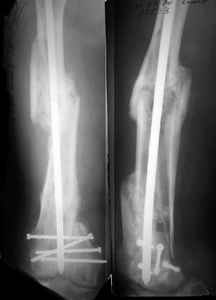

KEMMD> B. Fixation loosening: distal cutting of the nail, non-unions do happen

KEMMD> (cases attached).

The nail can be unlocked in the proximal fragment to prevent it.